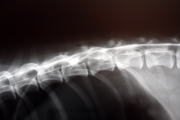

脊髄造影検査

レントゲン写真の中央の左から右に白い二本の線があります。この上の線が脊髄の上のラインとなり、下の線が脊髄の下のラインになります。下のラインのちょうど左右真ん中ぐらいで、線が上に窪んでいるのが解ると思います。この窪みが、飛び出してしまった椎間板です。

脊髄造影検査

レントゲン写真中央の上から下へ二本の白い線があります。(若干、わかりずらいかもしれません。)左側の線が中央あたりで、右側に窪んで線が不明瞭なのが解ると思います。この窪みが、飛び出してしまった椎間板です。以上の検査より右側の胸椎(背骨)11番目と12番目の間の椎間板が上に飛び出して脊髄神経を圧迫している事が、判明しました。手術により、椎弓という脊髄の上の天井の骨を削り、飛び出してしまった椎間板を除去し、無事、脊髄の圧迫を解除できました。